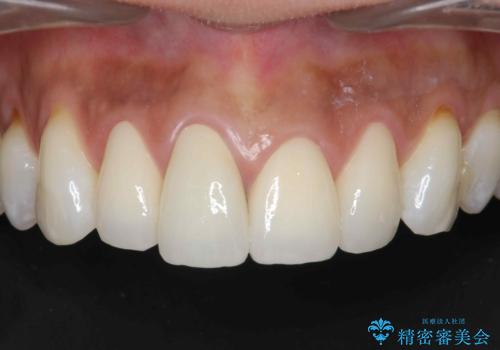

[ 審美歯科 ] 前歯セラミック治療の再治療

担当医 大元洋佑

![[ 審美歯科 ] 前歯セラミック治療の再治療の症例 治療前](https://seimitsushinbi.jp/wp/wp-content/uploads/2025/02/75321d6ba3daff4b7b0dad4b41050d2a-500x350.jpg?v=1739351948)

![[ 審美歯科 ] 前歯セラミック治療の再治療の症例 治療後](https://seimitsushinbi.jp/wp/wp-content/uploads/2025/02/072789f35cbfa80728bff15f84799af9-500x350.jpg?v=1739351952)